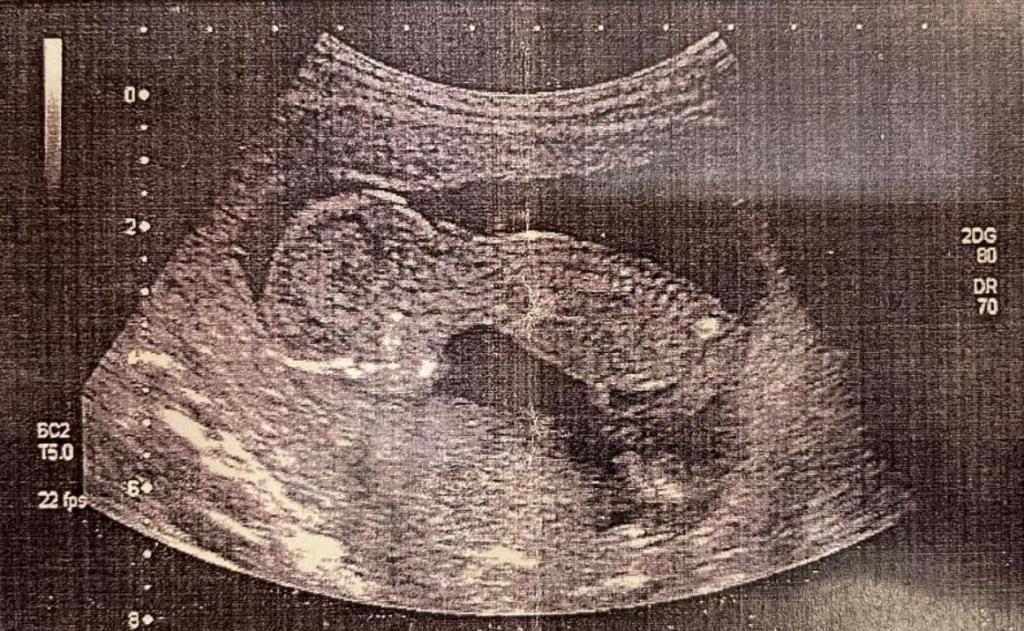

Viene infine condivisa l’ecografia di un feto (ricordiamo che a Bevilacqua mai nessun documento medico o clinico fu inviato e neanche fatto visionare, al contrario delle richieste di denaro con sottese minacce, come da audio già pubblicati, ndr).

Barbara ZP condivide la foto dell’ecografia di un “misterioso feto” con amici della chat di gruppo – Isabel, Alvaro Salvavidas, Matriarca

ed inizia una conversazione – con una “contemplazione” della “creatura” già abbastanza formata – seguita dalle rassicurazioni, da parte dell’amica dell’italo-brasiliana, del fatto di essere riusciti nel loro obiettivo.

B. E’ meravigliosamente magnifico!!!!!!!! (Barbara si riferisce alla foto del feto che condivide con gli “amici”, ndr)

A. ahah rilassati Formica (pseudonimo di Barbara nelle conversazioni con gli “amici”, ndr) sono sicura che non ha perso il fascino, è tutto di Alvaro, il prezioso seme è suo.